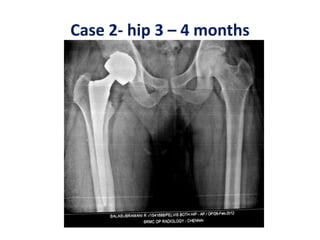

Case 2- hip 3 – 4 months

Case 2- hip3 – 4 months